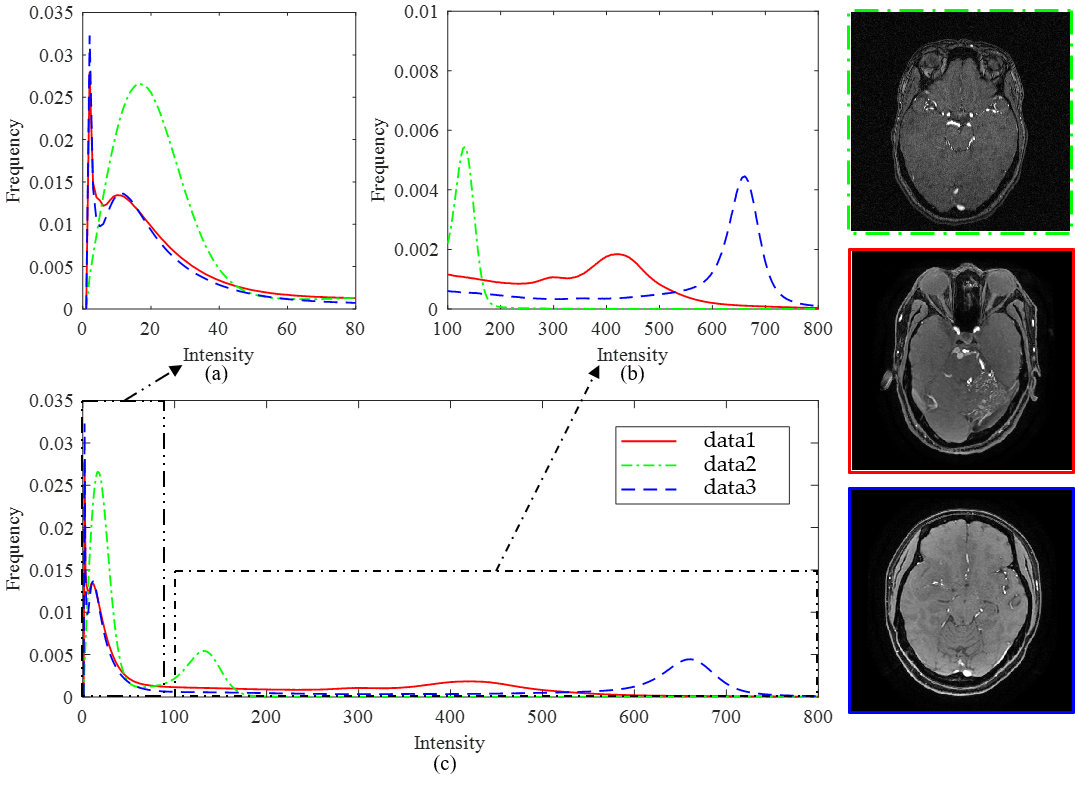

图一: 三个不同临床磁共振设备采集的数据直方图

现有的各类脑磁共振血管分割方法依赖于特定MR成像设备或特定数据集,基于模型驱动的血管分割方法通常不能完整地提取脑血管网络并且存在过分割现象,基于深度学习的方法受限于海量数据标注问题。上述两篇论文分别提出了两种鲁棒的统计学方法,实现任意磁共振设备型号下的TOF-MRA三维数据的全脑血管拓扑结构精确提取,如图一、二、三,该研究可以对深度学习方法提供血管数据的自动标注工具;在特定磁共振设备下,实现基于三维TOF-MRA和MR-T1数据的完整脑动脉和脑静脉结构的精确分割,如图四(f)。上述成果对于脑血管的自动标注、分割、临床可视化具有重要现实意义。